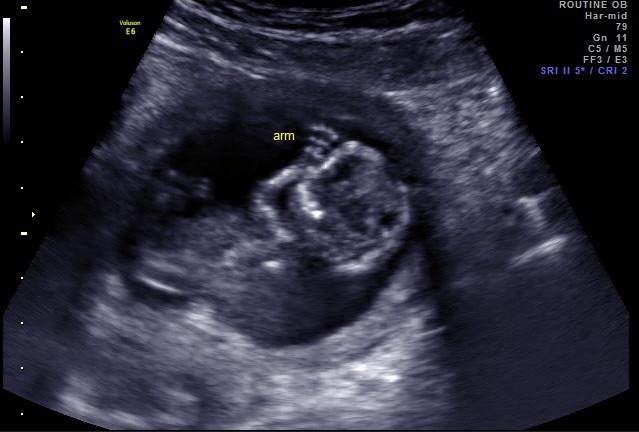

image